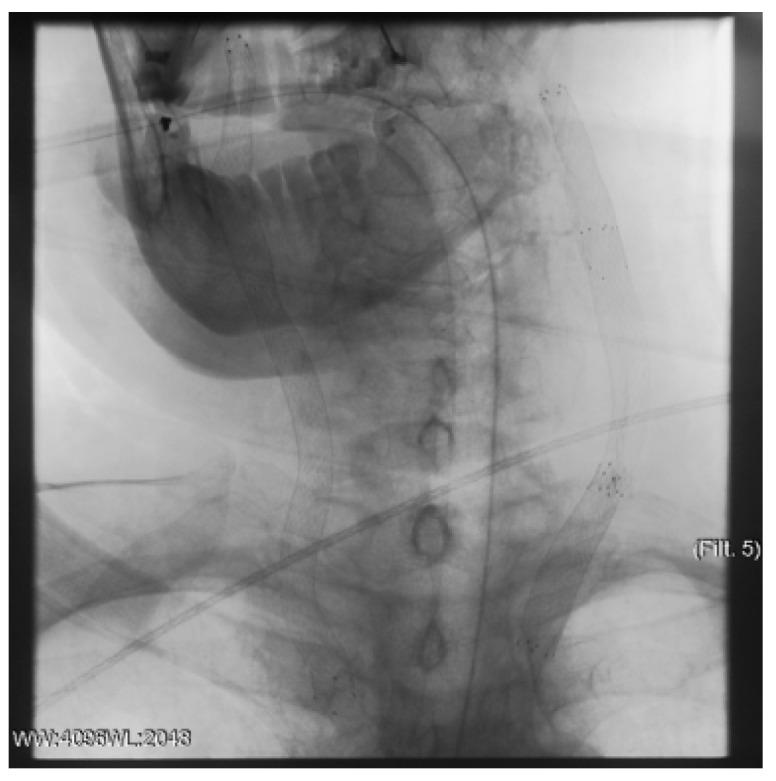

A type A aortic dissection (TAAD) is a dangerous condition requiring emergency surgery. Due to the similarity of the symptoms of cerebral malperfusion in TAAD and the signs of ischemic stroke, a differential diagnosis of these diseases is not always available. Patients with TAAD after cerebral malperfusion can have a neurological deficit. Thrombolysis is performed in this case. It can worsen the patient's condition and increase the risk of mortality and disability. The aim of the study is to evaluate the new approach to restoring cerebral perfusion during aortic dissection. This approach includes endovascular recanalization and carotid stenting.

Two clinical cases of TAAD complicated by cerebral malperfusion are described. The first patient is 73 years old and was admitted as planned to perform transcatheter aortic valve implantation (TAVI) for grade III aortic stenosis. The patient underwent transcatheter aortic valve implantation (TAVI) on the second day after admission. The second patient is 60 years old and was hospitalized by an ambulance with strong hypertension and ischemia. The surgical correction of aortic dissection was postponed until the neurological status assessment in both patients.

The surgery to correct the aorta dissection was deemed inappropriate. The carotid arteries have been reanalyzed, and cerebral perfusion has been restored in a short time in both patients.

Acute bilateral internal carotid occlusion is a potentially fatal TAAD outcome. Emergency endovascular recanalization and carotid stenting may be considered one of the few ways to restore cerebral perfusion.